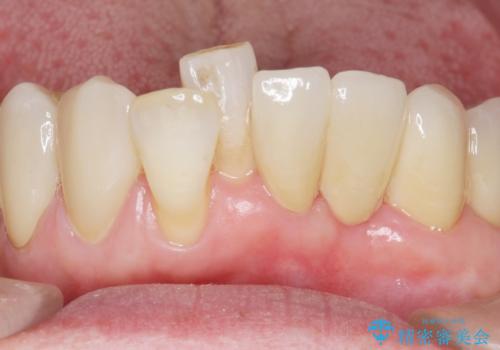

気にされていた前歯と奥歯の動揺がなくなったことと自然な仕上がりに喜んで頂けました。

クラウンの種類:オールセラミッククラウン スタンダード

入れ歯も抵抗があるとのことから、相談を重ね、今の状態では保存不可能な下の前歯(左下2)を抜去し、ブリッジや連結補綴により動揺を抑えることにしました。

また、咬み合わせが反対になっている上の前歯(左上2)も補綴で形を変えることにより、咬合を改善しました。